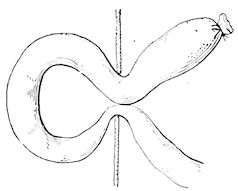

| Colic due to invagination | 163 | |||

| Colic as a result of strangulation | 167 | |||